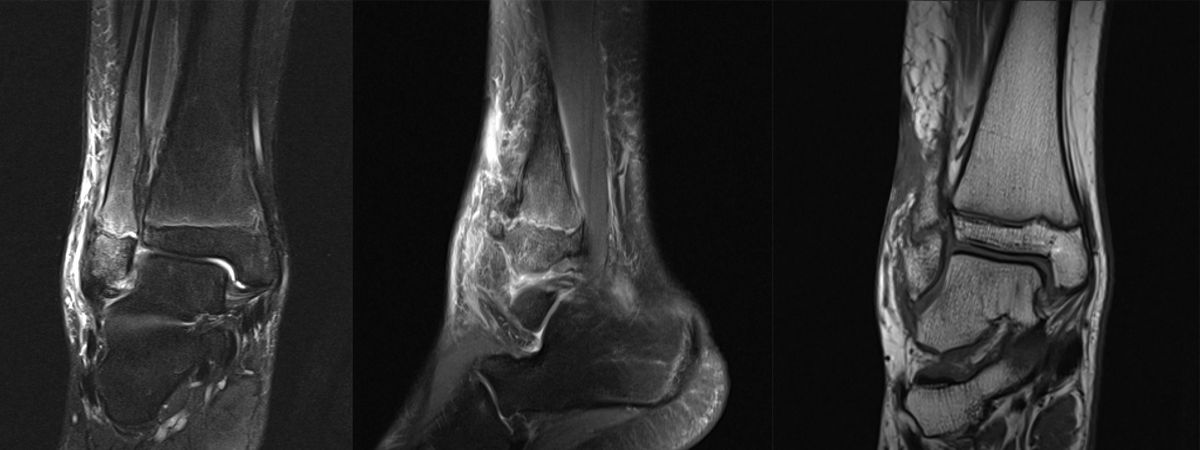

MRT

Die Kernspintomographie hat ihre Stärke in der Darstellung von Weichteilverletzungen. Insbesondere Verletzungen der Wachstumsfuge, des Periosts und der Bänder lassen sich gut visualisieren. Nachteilig ist die Untersuchungsdauer von 20-30 Minuten. Bleibt das Kind während dieser Zeit nicht ruhig liegen, kommt es zu Bewegungsartefakten, welche die Beurteilbarkeit der Bilder beeinträchtigen.